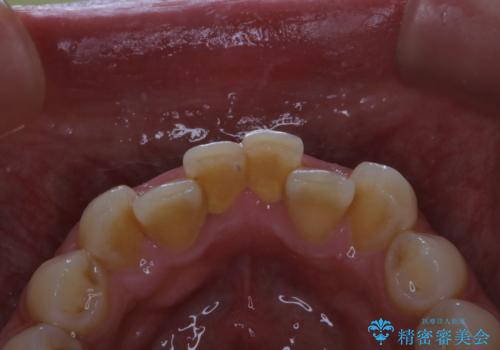

- 歯科でのクリーニングが5・6年ぶりで、全体をきれいにしたいとのことで来院されました。PMTC60分コースを行いました。

PMTCとは「Professional Mechanical Tooth Cleaning」の略で、専用の機器を使った歯のクリーニングです。

PMTCは誰もが実施できるというわけではなく、歯科医師や歯科衛生士によるプロフェッショナルケアです。

審美的面だけではなく、歯周病や虫歯・口臭などのリスクを予防することができます。

汚れを除去することにより、症状の早期発見につながります。